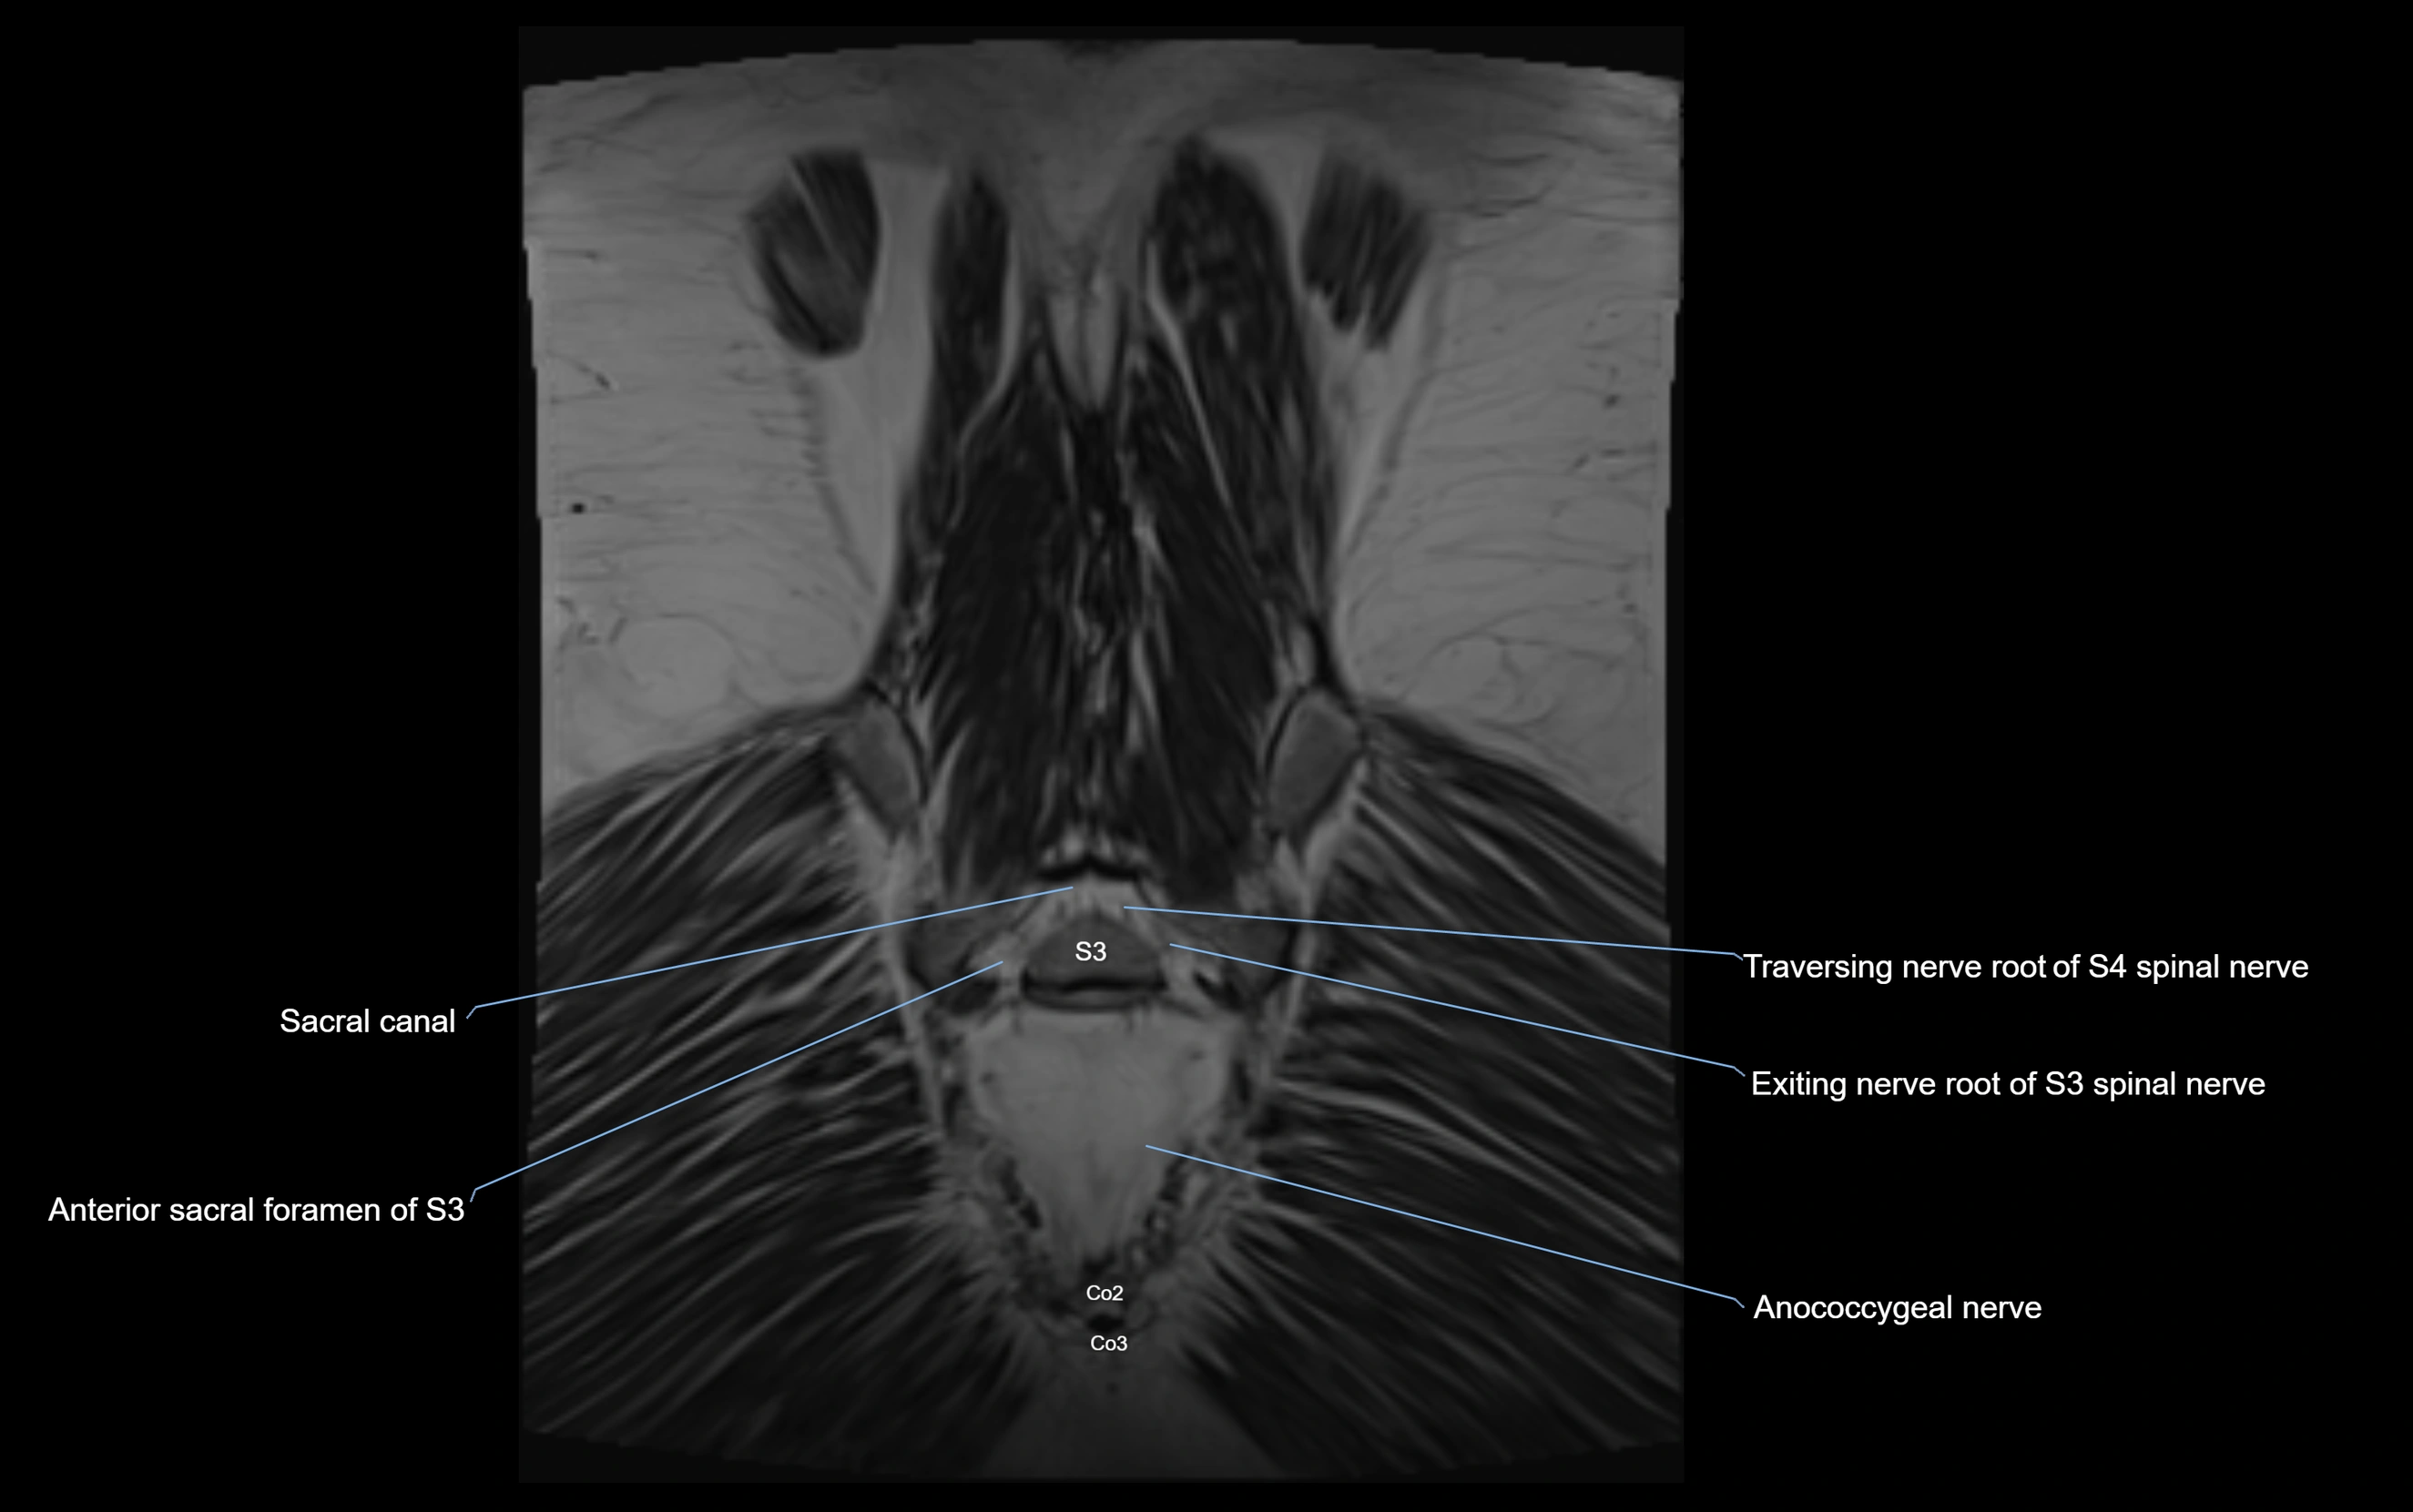

Anococcygeal nerve

The anococcygeal nerve is a small sensory nerve derived from the coccygeal plexus, which itself is formed by the ventral rami of S4, S5, and the coccygeal nerve (Co1). Although tiny, this nerve plays an important role in supplying the skin of the coccyx and the area between the anus and coccyx. It passes through the sacrotuberous ligament and runs in the midline behind the coccyx.

Despite its small size, the anococcygeal nerve is clinically important because of its involvement in coccygodynia (coccyx pain) and perineal pain syndromes.

Origin, Course, and Branches

• Origin:

• Arises from the coccygeal plexus, formed by ventral rami of S4, S5, and Co1

• Course:

• Emerges through the sacrotuberous ligament near the coccyx

• Runs in the midline posterior to the coccyx

• Passes forward into the small space between anus and coccyx

• Branches:

• Small cutaneous branches that supply the skin between the coccyx and anus

MRI Appearance

T1-weighted images:

• Nerve appears as a very thin low-to-intermediate signal intensity structure

• Surrounded by bright fat, aiding visualization

T2-weighted images:

• Nerve shows intermediate to mildly hyperintense signal compared to muscle

• Pathological involvement appears brighter

3D T2 SPACE / CISS:

• Nerve appears intermediate to mildly hyperintense compared to muscle

• Surrounded by bright fat or CSF, improving visualization

• Best sequence for mapping small pelvic nerves such as the anococcygeal

MRI image

image